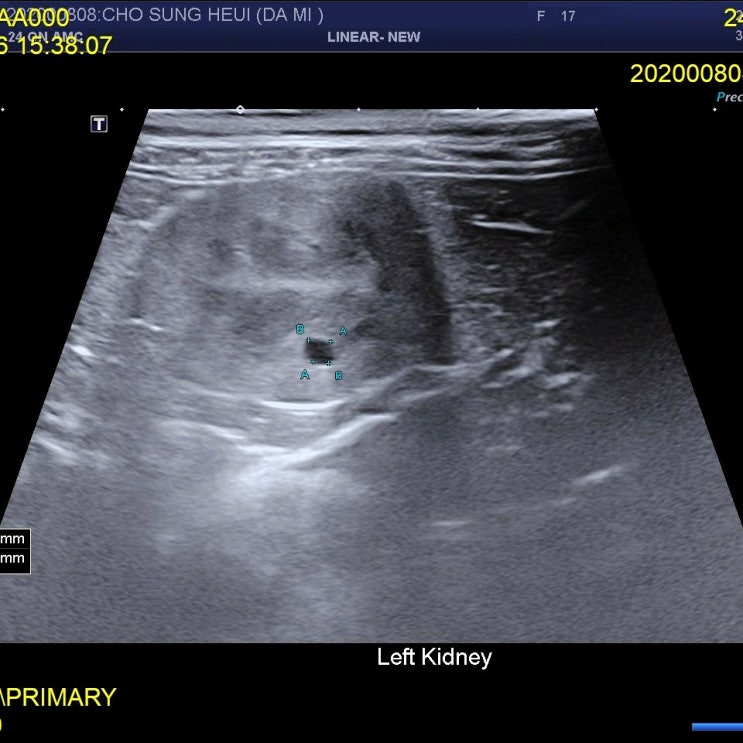

약 3개월 만의 병원방문 후기

오늘 드디어 병원을 방문하는 날이다. 사실 어제부터 일도 손에 안잡히고 좌불안석 이었다. 평소같으면 오...

3개월만의 병원방문 D-1

다미는 17살이다. 2007년 2월생이니 4개월이 지나면 18살이 된다. 많은 노묘가 그렇듯 다미도 신부전이 있...